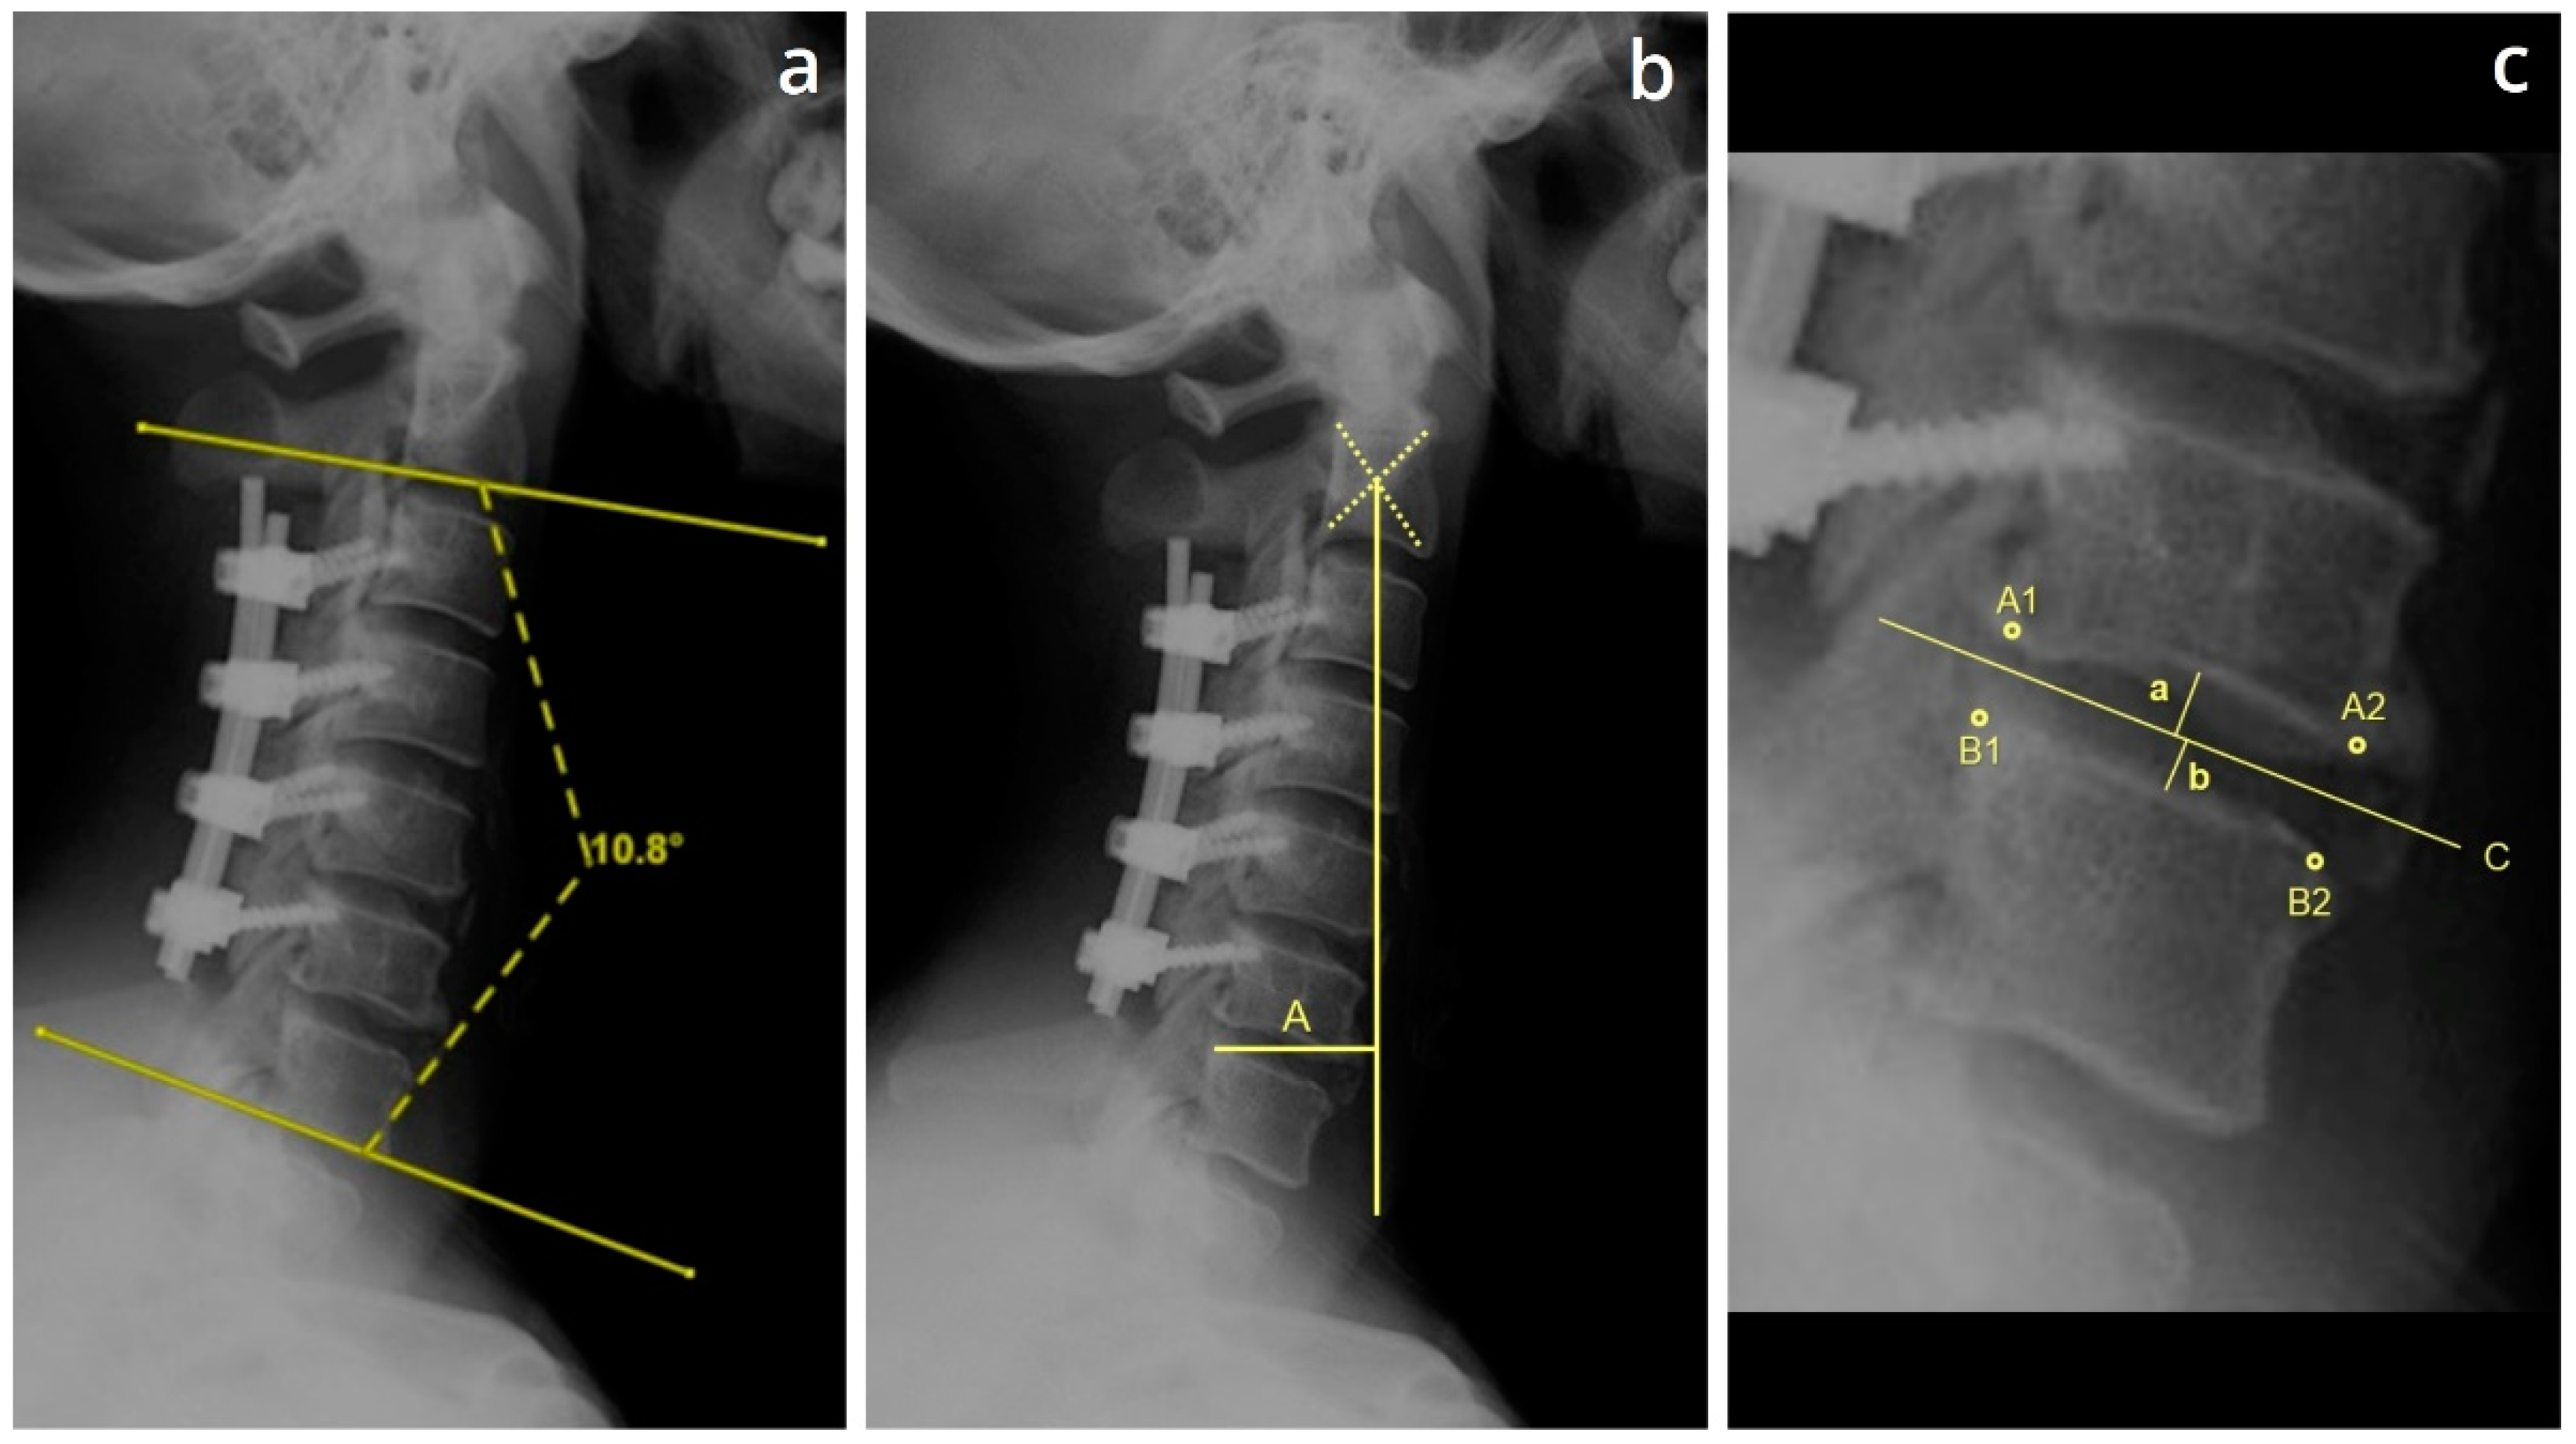

2.3. Definition of the Cervical Parameters

Cervical lordosis was defined as the cobb angle between the lower endplates measured from C2 to C7 (Figure 1a) [13]. C2–7 SVA was the distance from the posterosuperior corner of C7 to a vertical line from the center of the C2 vertebrae (Figure 1b) [13]. The disc height was measured at the midpoint of two adjacent endplates (Figure 1c) [14]. In cases where the X-rays were not clear (predominantly, for lower cervical and upper thoracic region), the disc heights were measured on CT scans.

Figure 1. Measurements. (a) Visual representation of the technique used to measure the cervical C2–7 Cobb angle, defined as the angle between the lower endplates of the C2 and C7 vertebra. (b) Visual representation of the technique used to measure the cervical C2–7 sagittal vertical axis (SVA), defined as the distance between the plumb line dropped from centroid of C2 and the posterior superior corner of C7, marked as A in the Figure. (c) Method used to measure the disc height on plain radiography and computed tomography images. The 4 corners of the adjacent vertebrae are marked A1, A2, B2, B2. A straight bisecting line C was drawn through the centers of A1/B1 and A2/B2. The sum of the shortest distances from the midpoint of the upper and lower endplates to the bisecting line corresponds to the disc height (a + b).